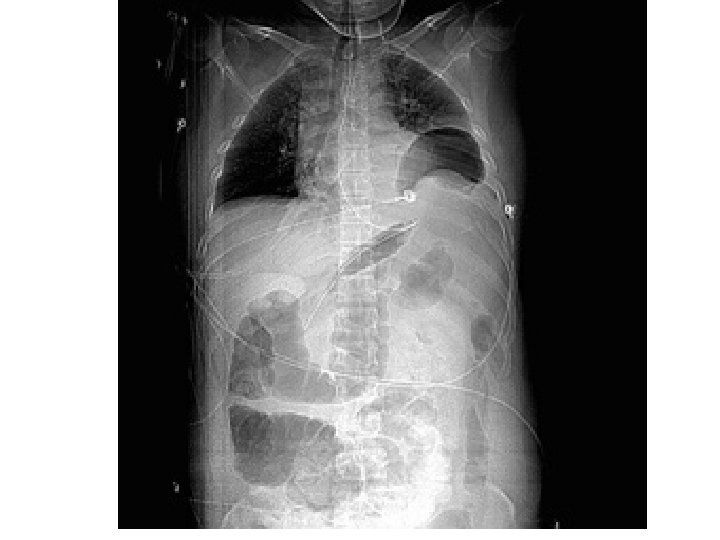

Hemotoraks

PULMONER KONTÜZYON